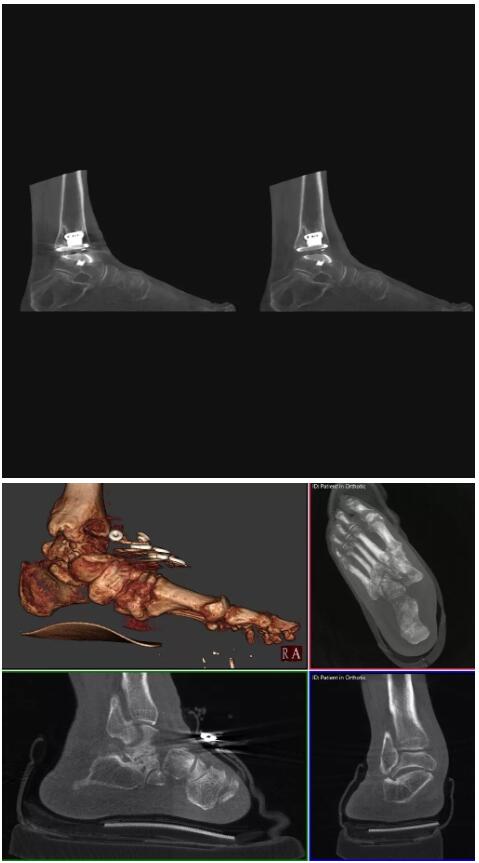

另外一款被稱為世界上最小的CT,它的重量僅300磅,不僅能夠掃查足部,還可以檢查膝蓋和上肢等。

與上面介紹的CT一樣,它同樣具有輻射低、占地空間小(23*36)的特點,隨開隨用(支持直接接入墻上的插座)。

這款CT使用非常方便,通過上下移動保持與患者的手臂或者雙腿齊平,掃描快速,僅需要30秒左右就可以完成掃查。

以上介紹的CT均來自國外同一家公司,這些CT均配置了可視化軟件,可以進行切片、3D重建以及大型CT附帶的所有典型的操作功能。

以下是這些“特立獨行”的CT所拍出來的圖像: